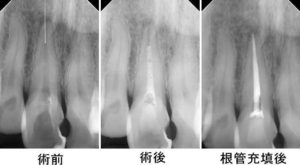

2017年10月10日 根管治療(根の治療・神経の治療)歯内療法 2021年9月12日 坂詰歯科医院 当院の根管治療の症例集 埼玉県行田市坂詰歯科医院(熊谷,羽生,鴻巣,桶川,北本,加須,深谷,蓮田,久喜,伊奈町,東松山市,館林,太田,佐野,蕨,川口,さいたま市からも来院)が歯を抜かない根管治療(根の治療)、マイクロスコープを使った保険診療の根管治療(神経の治療)、ラバーダム防湿、長く続く痛み、歯性上顎洞炎、外科的歯内療法(歯根端切除術)、フィン、MTA治療を解説。担当Drは川口市(蕨市より)出身。